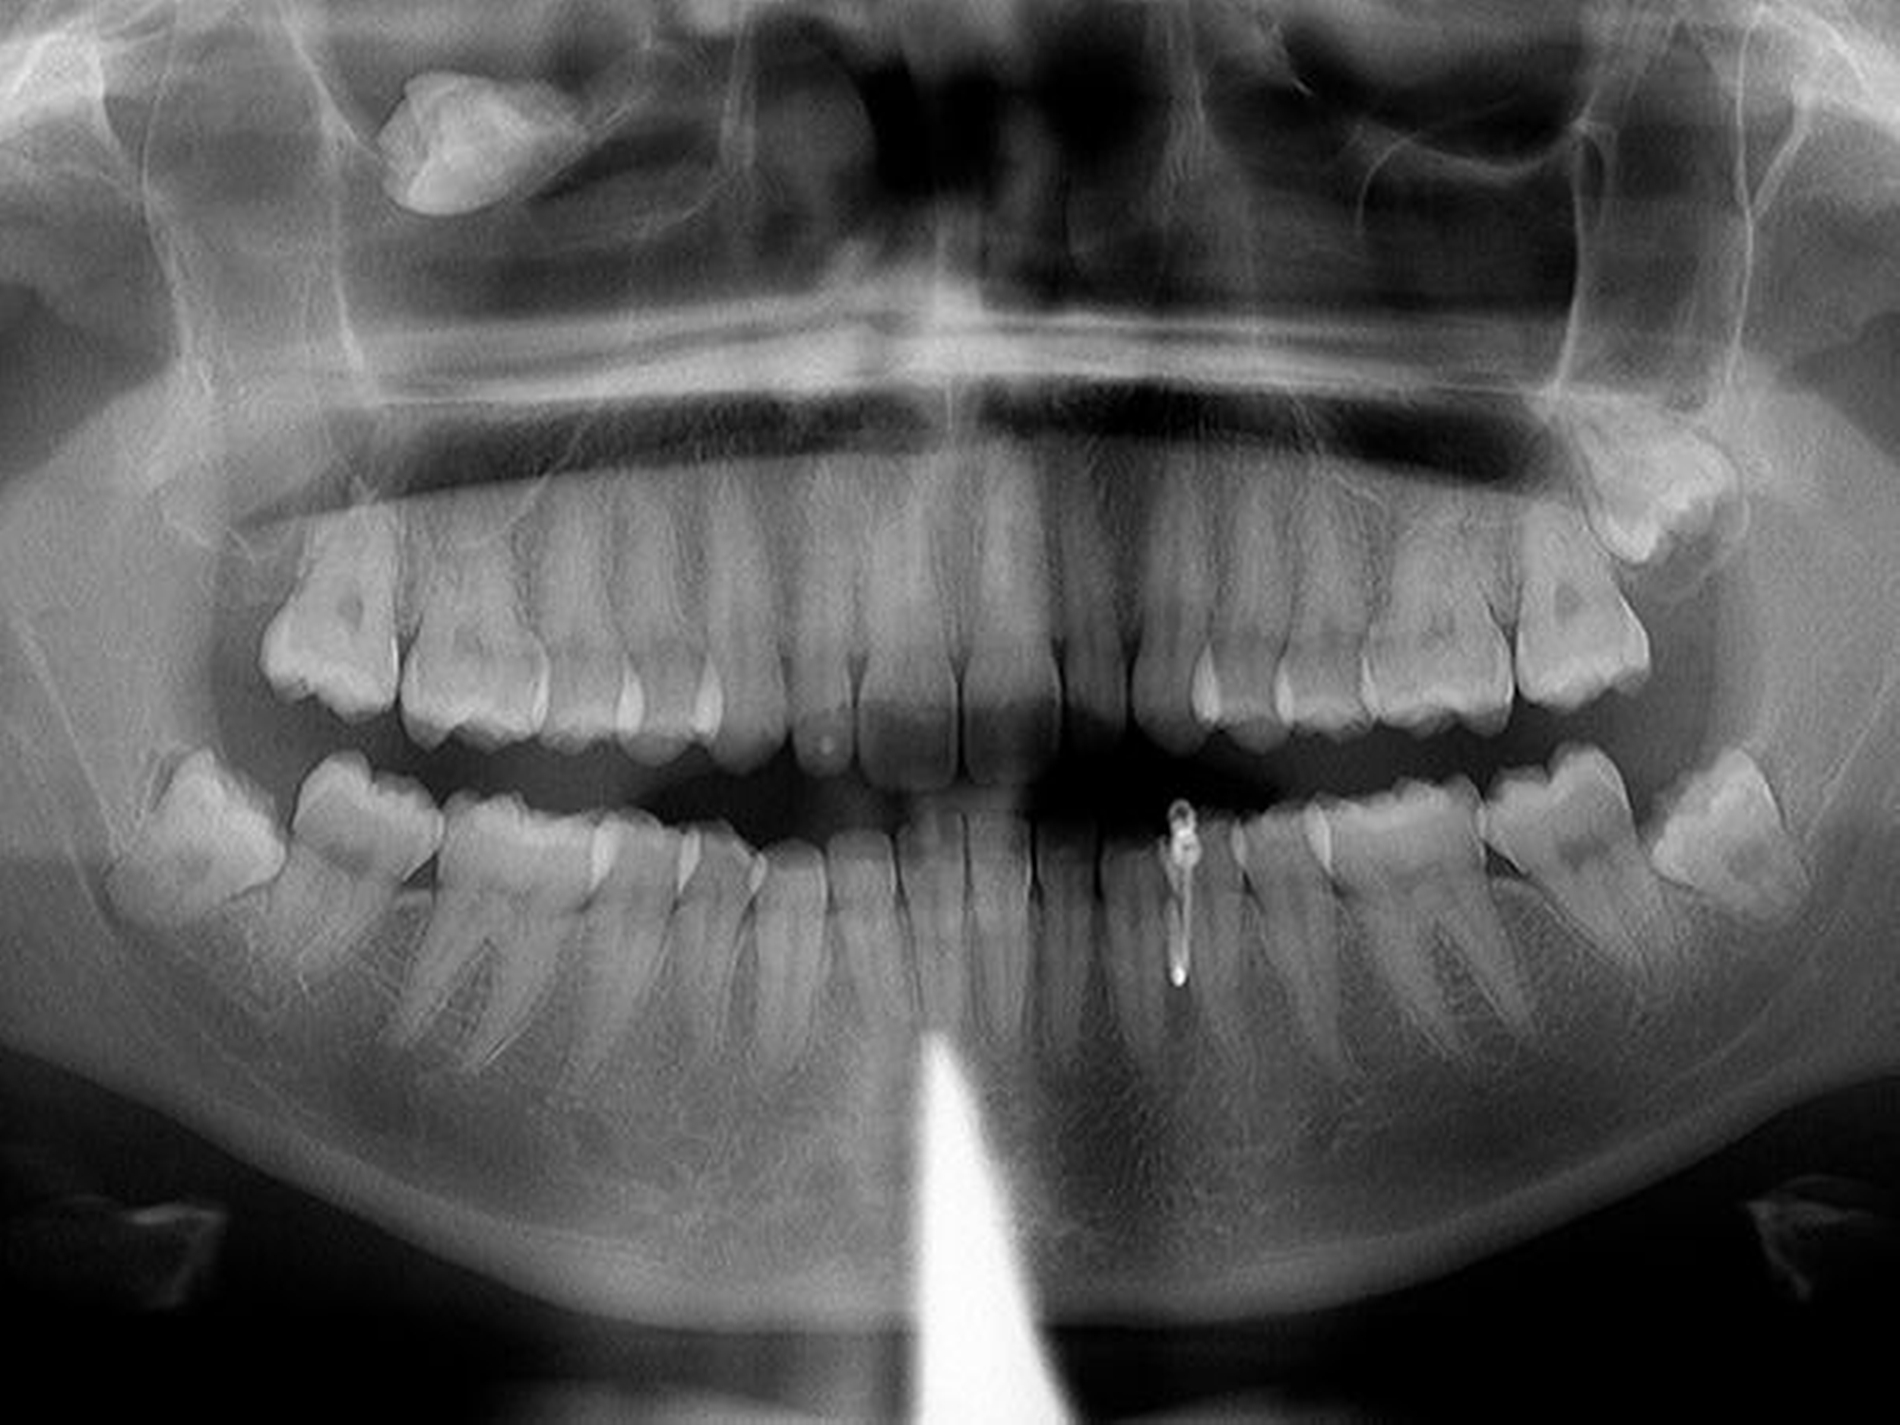

Röntgen (OPG Abb.1): verschattete Kieferhöhle rechts mit extrem verlagertem Zahn 18 direkt infraorbital

Differenzialdiagnostisch stand so der Verdacht auf eine atypische Neuralgie im Bereich des Nervus infraorbitalis rechts (im Sinne einer Trigeminusneuralgie) im Raum. Anamnestisch – die junge Frau war seit ihrem vierten Lebensjahr in unserer Praxis Patientin – war schon eine Dentitio tarda diagnostiziert. Da aber im Bereich des I. Quadranten bereits ein verlagerter Weisheitszahn 18 bekannt war, wurden zunächst folgende weitere Befunde erhoben: